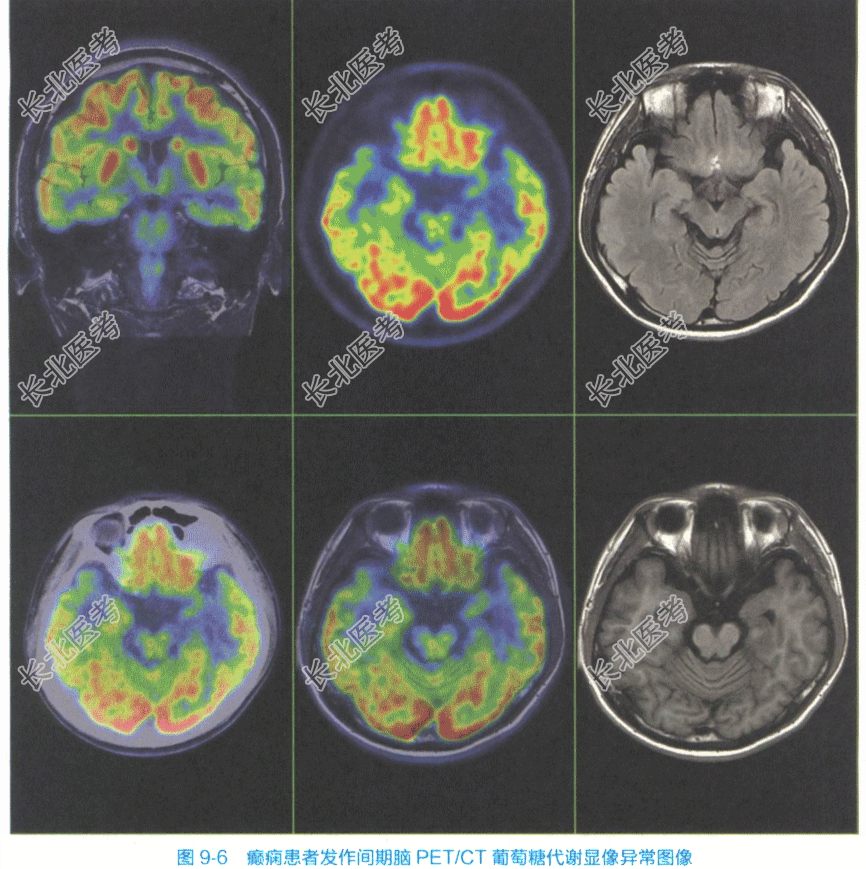

- [材料题] 患者,男,24岁,因发作性四肢抽搐伴意识丧失20余年入院。头颅CT平扫未见异常。为进一步明确癫痫病因行脑部葡萄糖代谢显像。受检者禁食4~6h,保持安静,戴黑眼罩和耳塞进行视听封闭,静脉注射¹⁸F-FDG3.70MBq/kg(0.10mCi/kg),45min后行PET/CT脑葡萄糖代谢显像。数据经软件重建获得¹⁸F-FDG在脑内分布的横断面、冠状面和矢状面图像。检查表现:左侧海马显像剂分布减低;CT未见海马异常密度改变,MRI示左侧海马体积缩小,T2Flair信号增高。